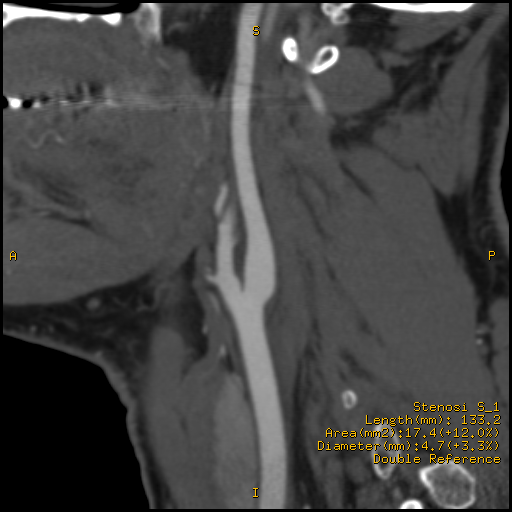

angio CT carotide

Sezione sagittale